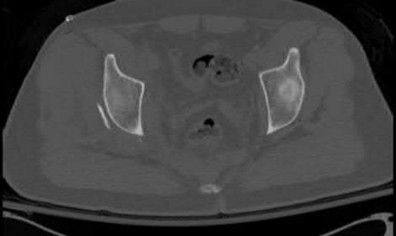

A poly-trauma patient presents hemodynamically unstable with an anteroposterior compression (APC-III) pelvic ring injury. A circumferential pelvic binder is requested to reduce pelvic volume and control hemorrhage. To be anatomically effective, the binder must be centered precisely over which of the following landmarks?

Correct Answer: Greater trochanters

Explanation:

For optimal mechanical advantage and effective reduction of an 'open book' pelvic fracture (APC type), a pelvic binder must be applied directly over the greater trochanters of the femurs. Applying it higher, such as over the iliac crests, is a common error that fails to adequately close the pelvic ring and can paradoxically open the true pelvis.